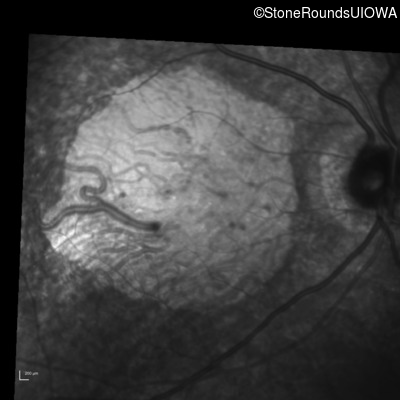

Infrared Fundus Photograph - Right - 20/250 sc

Exemplar